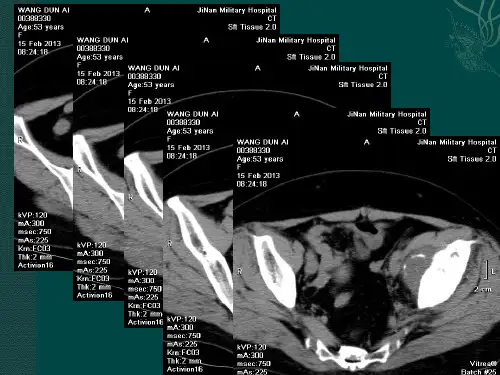

CT 检查: 适合显示软骨基质内的钙化和皮质 的情况,其显示骨质破坏部位、范围、形 态优于X线平片。软骨肉瘤常见CT表现 为骨髓腔内分叶状肿块并伴有“环弧状” 或“砂砾样”钙化;若肿瘤侵犯骨髓,其CT 值明显增高,与正常骨髓脂肪的低密度形 成明显对比;CT 增强扫描可显示肿瘤周边 及肿瘤内间隔轻度强化。